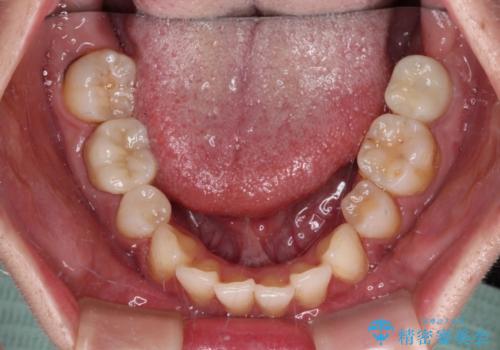

部分矯正を併用した奥歯のインプラント治療

- 左下欠損部のインプラント治療と、右下の歯の痛みを気にして来院された患者様です。

ただし、長期間欠損を放置していたことで、咬み合う上の奥歯が動いてしまっていたので、まずは上顎奥歯の部分矯正を行い、より理想的な咬み合わせを目指すこととしました。

まず生活歯髄療法を行い、その後部分矯正やインプラント処置を行いましたが、最初の処置から1年以上経っても右下奥の処置歯の神経組織に異常は認められませんでした。

部分矯正を行ったことで、違和感のない咬み合わせを達成することができました。